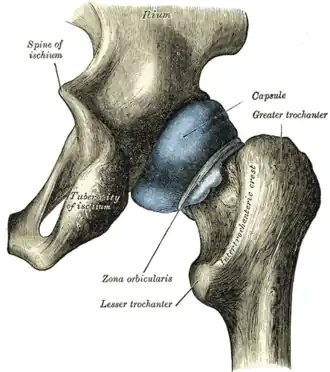

En bleu, le croissant encroûté de cartilage.

La capsule articulaire entoure toute la tête fémorale en s'insérant à distance du cartilage : en avant le long de la ligne inter-trochantérique et en arrière à la jonction du tiers latéral et des deux-tiers médiaux du col fémoral.

Du côté de l'os coxal, elle s'insère sur la face externe du labrum acétabulaire et sur le pourtour de l'acétabulum.

Elle est constituée de fibres longitudinales et de fibres circulaires. Ces dernières constituent la zone orbiculaire de l'articulation coxale.

La capsule est renforcée par trois ligament extra-articulaire :

- le ligament ilio-fémoral, antérieur, qui unit l'épine iliaque antérieure et inférieure au petit et au grand trochanter en se dédoublant en deux faisceaux en Y inversé,

- le ligament pubo-fémoral, antérieur et inférieur, qui relie la branche supérieure du pubis à la ligne inter-trochantérique.

- le ligament ischio-fémoral, postérieur, qui relie la partie supérieure de la tubérosité ischiatique à la crête inter-trochantérique.

La partie inférieure du labrum acétabulaire prend une structure fibreuse au niveau de l'incisure de l'acétabulum formant le ligament transverse de l'acatabulum. Il renforce le maintien de la tête fémorale dans la cavité cotyloïde.

Un ligament intra-articulaire, mais extra-synovial, le ligament de la tête du fémur relie la fossette de la tête du fémur aux deux cornes de la surface lunaire et au ligament transverse de l'acétabulum. Son rôle mécanique est minime mais il permet à la branche acétabulaire de l'artère obturatrice d'irriguer la tête fémorale.